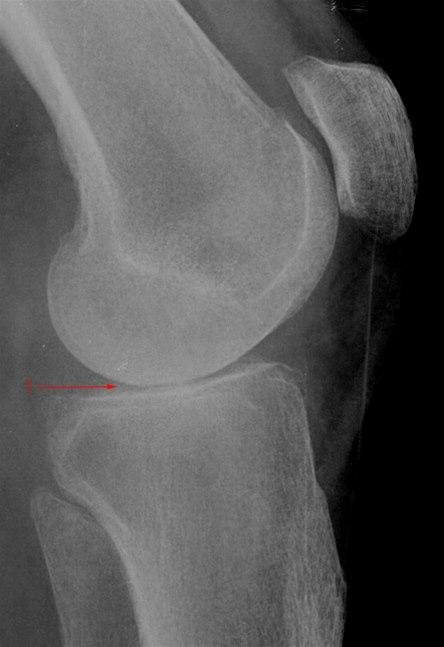

Gonartrose, moderat, side

Lett redusert bruskhøyde i kneleddet (1).